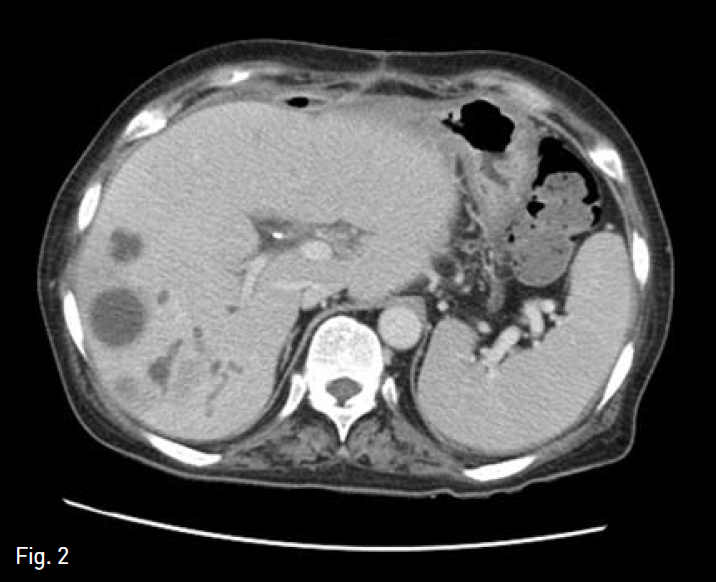

Fig. 2

Follow-up axial abdominal CT image, obtained 2 months after operation, shows multiple small low attenuated lesions with in trahepatic bile duct dilatation.